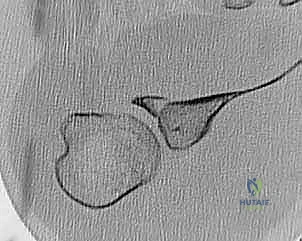

الخطوة 3: زرع الخطاطيف العظمية (Suture Anchors Insertion)

يقوم الجراح بزرع خطاطيف أو مثبتات دقيقة جداً (مصنوعة من مواد تذوب حيوياً أو من التيتانيوم) في حافة العظم الحقاني. هذه الخطاطيف محملة بخيوط جراحية فائقة القوة.

الخطوة 4: إصلاح بانكارت (Bankart Repair)

يتم تمرير الخيوط الجراحية بمهارة عالية عبر الشفا الحقاني الممزق والأربطة المنفصلة. يتم ربط هذه الخيوط بإحكام لشد الأنسجة الممزقة وإعادتها إلى مكانها التشريحي الأصلي على حافة العظم، مما يعيد بناء "المصد" الأمامي الذي يمنع خلع الكتف.